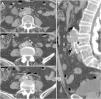

El estudio basal es imprescindible para la valoración de complicaciones aneurismáticas que podrían originar una FAE, como el hematoma intramural y el desplazamiento central de calcificaciones intimales en la úlcera penetrante (fig. 7). Es frecuente identificar asimismo contenido endoluminal de alta atenuación en relación con restos hemáticos.

Fístula aortoesofágica primaria en varón de 67 años con hematemesis, sudoración profusa, palidez cutánea e hipotensión. La tomografía computarizada basal (A) muestra una dilatación esofágica con contenido intraluminal de alta atenuación en relación con componente hemático (*) y desplazamiento de calcificaciones intimales que indica rotura de placa ateromatosa con puerta de entrada (flecha). La fase arterial en plano axial (B), reconstrucción sagital (C) y volumétrica (D) muestra calcificaciones en la pared de la aorta descendente y una dilatación sacular (punta de flecha) que contacta con la pared esofágica sin plano graso de separación. Estos hallazgos sugieren úlcera penetrante. A pesar de la ausencia de extravasación de contraste intravenoso, se confirmó la presencia de fístula aortoentérica en la cirugía.

Recientemente, Kennedy et al. han descrito el desarrollo de un abombamiento de nueva aparición en la vertiente anterior/anterolateral de la aorta en la proximidad de un asa intestinal vecina como signo precoz de FAE23 (fig. 8). En presencia de trombo excéntrico este hallazgo podría ser menos evidente. Sin embargo, se trata de un estudio retrospectivo sin grupo de control que no permite valorar la incidencia de este signo en la población general, por lo que debe ser valorado con cautela.

Fístula aortoduodenal primaria en varón de 65 años con episodio de vómitos intermitentes y melenas de 2 semanas de evolución que acude a Urgencias con hematemesis, mareo e hipotensión. La tomografía computarizada basal (A, B) demuestra contenido de alta densidad (47 UH) en la cámara gástrica en relación con coágulo y un aneurisma calcificado en aorta abdominal con hematoma intramural. La fase arterial (C) revela un abombamiento sacular en la cara anterolateral de la aorta con pérdida del plano graso de separación con el duodeno (*). En fase tardía (D) no se demuestra clara extravasación de CIV. La laparoscopia confirmó la presencia de FAE (E) (a: aorta; d: duodeno; f: fístula) que fue reparada en el mismo acto quirúrgico (F) incluyendo resección segmentaria del duodeno.